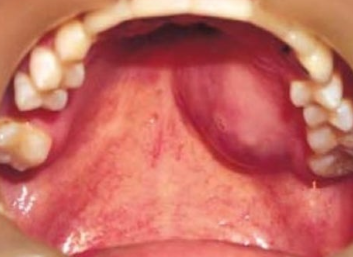

침샘암의 가장 대표적인 초기 증상은 통증이 없는 몽우리가 침샘 부위에 만져지는 것입니다. 이는 많은 사람들이 놓치기 쉬운 신호입니다. 통증이 없기 때문에 대수롭지 않게 여기거나 단순한 염증으로 오해하기 쉽기 때문입니다.

침샘에 발생된 종양은 대부분 서서히 자라며, 귀밑 몽우리나 턱 밑, 혀밑 등에 덩어리로 나타납니다. 손으로 만졌을 때 움직이고 혹처럼 만져진다는 특징이 있으며, 얼굴이나 목 부위에 덩어리가 만져져서 병원을 찾는 경우가 일반적입니다.

악하선(턱밑샘) 암의 경우

- 턱 밑의 무통성 종물

- 구강저의 종물